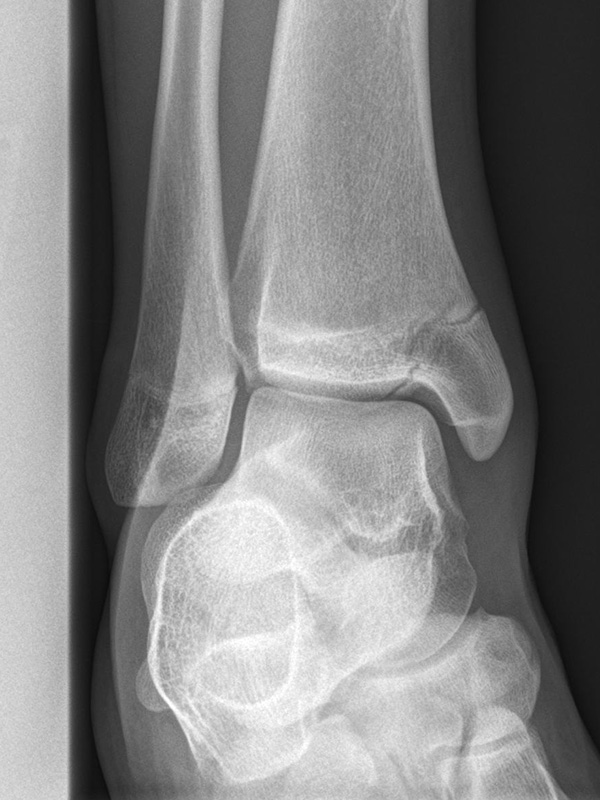

Sprunggelenk lateral ohne Belastung

Positionierung:

• Patient liegt auf dem Rücken und dreht den Fuß des aufzunehmenden Beins so nach innen, dass beide Malleolen genau übereinanderstehen.

• Die laterale Fuss-Seite liegt auf der Kassette, das Sprunggelenk ist 90° angewinkelt.

• Der Zentralstrahl wird zentral auf das Sprunggelenk gerichtet.

Kennzeichen des Röntgenbildes:

• Oberes und unteres Sprunggelenk sind rein seitlich abgebildet, inklusive Kalkaneus.

• Die Malleolen kommen übereinander zu liegen.

• Tibiagelenkfläche und Talusrolle werden exakt seitlich dargestellt, es kommt zu keinen Doppelkonturen.

• Die Fibula projiziert sich ins mittlere bis hintere Drittel der Tibiagelenkfläche.

• Die vordere und hintere Tibiakante, das Chopart-Gelenk und das Subtalargelenk kommen zur Darstellung.

• Das proximale Ende des Os metatarsale V ist mit abgebildet.

• Der Weichteilmantel (Achillessehne) ist erkennbar.

Besondere Bemerkungen zum Beispielbild:

• Patient mit anamnestisch chronischer OSG Instabilität.

• Ventral der Tibia findet sich ein abgebrochener Osteophyt.

Zur Vollansicht und zum Lesen der Bildbeschreibung bitte die Bilder anklicken.